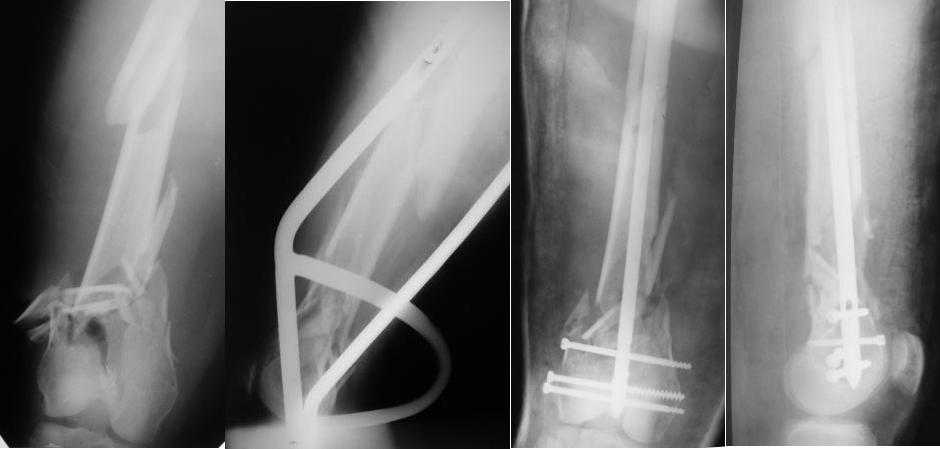

Re: Многооскольчатый перелом бедра

Какой смысл использовать тибиальный стержень на бедре?

И вообще мне кажется, что представленный ОС не допустим:1. стержень в суставе,2. неправильная длинна винтов, 3. ось конечности неправильная, 4. циркулярная гипсовая повязка после ОС?????

-1. стержень в суставе,

Это не критично, в межмышелковой борозде,не на опроной поверхности, выступает из субхондральной кости, не факт что из хряща.Про надколенник Александр Николаевич уже писал.

-2. неправильная длинна винтов,

и толщина тоже. При такой длине хочется помощнее.

-3. ось конечности неправильная,

Вполне прилично. Если в боковой проекции рекувации нет. Где кстати боковая, хочется спросить у постмейкера.

- 4. циркулярная гипсовая повязка после ОС?????

К сожалению, автор умалчивает. Думается, что в данном случае можно и без гипса.

Затем, что результаты как минимум не хуже, чем при использовании глубокоспециализированных DFN. Другое дело, что найти толстый тибиальный гвоздь больше 11м не всегда просто. В показаном примере он бы не подошел. Трочал бы сильнее из колена или при полном погружении отверстия пролетели бы проксимальнее перелома. Он показан больше для нижней трети, чем для области метафиза. Да и желательно чтобы винты толстые были, толще чем для тибии.

2. Лучше борется с рекурвацией дистального отломка за счет угла Герцога.(В представленном примере "недопобороли")

Приносим извенения за недостаток информации. Выкладываю все снимки. Стержень фирмы НПО ДЕОСТ(г.Пущино-на-оке)

Больная госпитализирована с тяжелой сочетанной травмой. Плюсом к перелому бедра имеется разрыв связок коленного сустава.